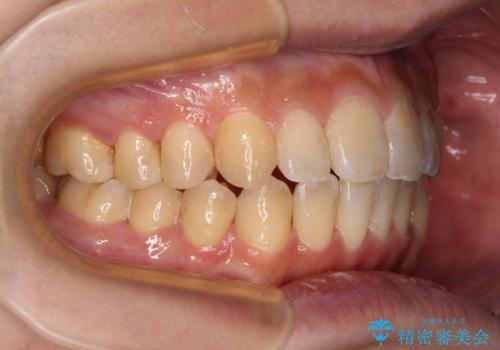

修復治療後に細かい部分をインビザラインで再度仕上げるプランとしました。

銀歯のセラミック治療が1番の希望であったため、ここまで歯列がきれいに整うとは思ってなかったようで、大変喜んでいただけました。